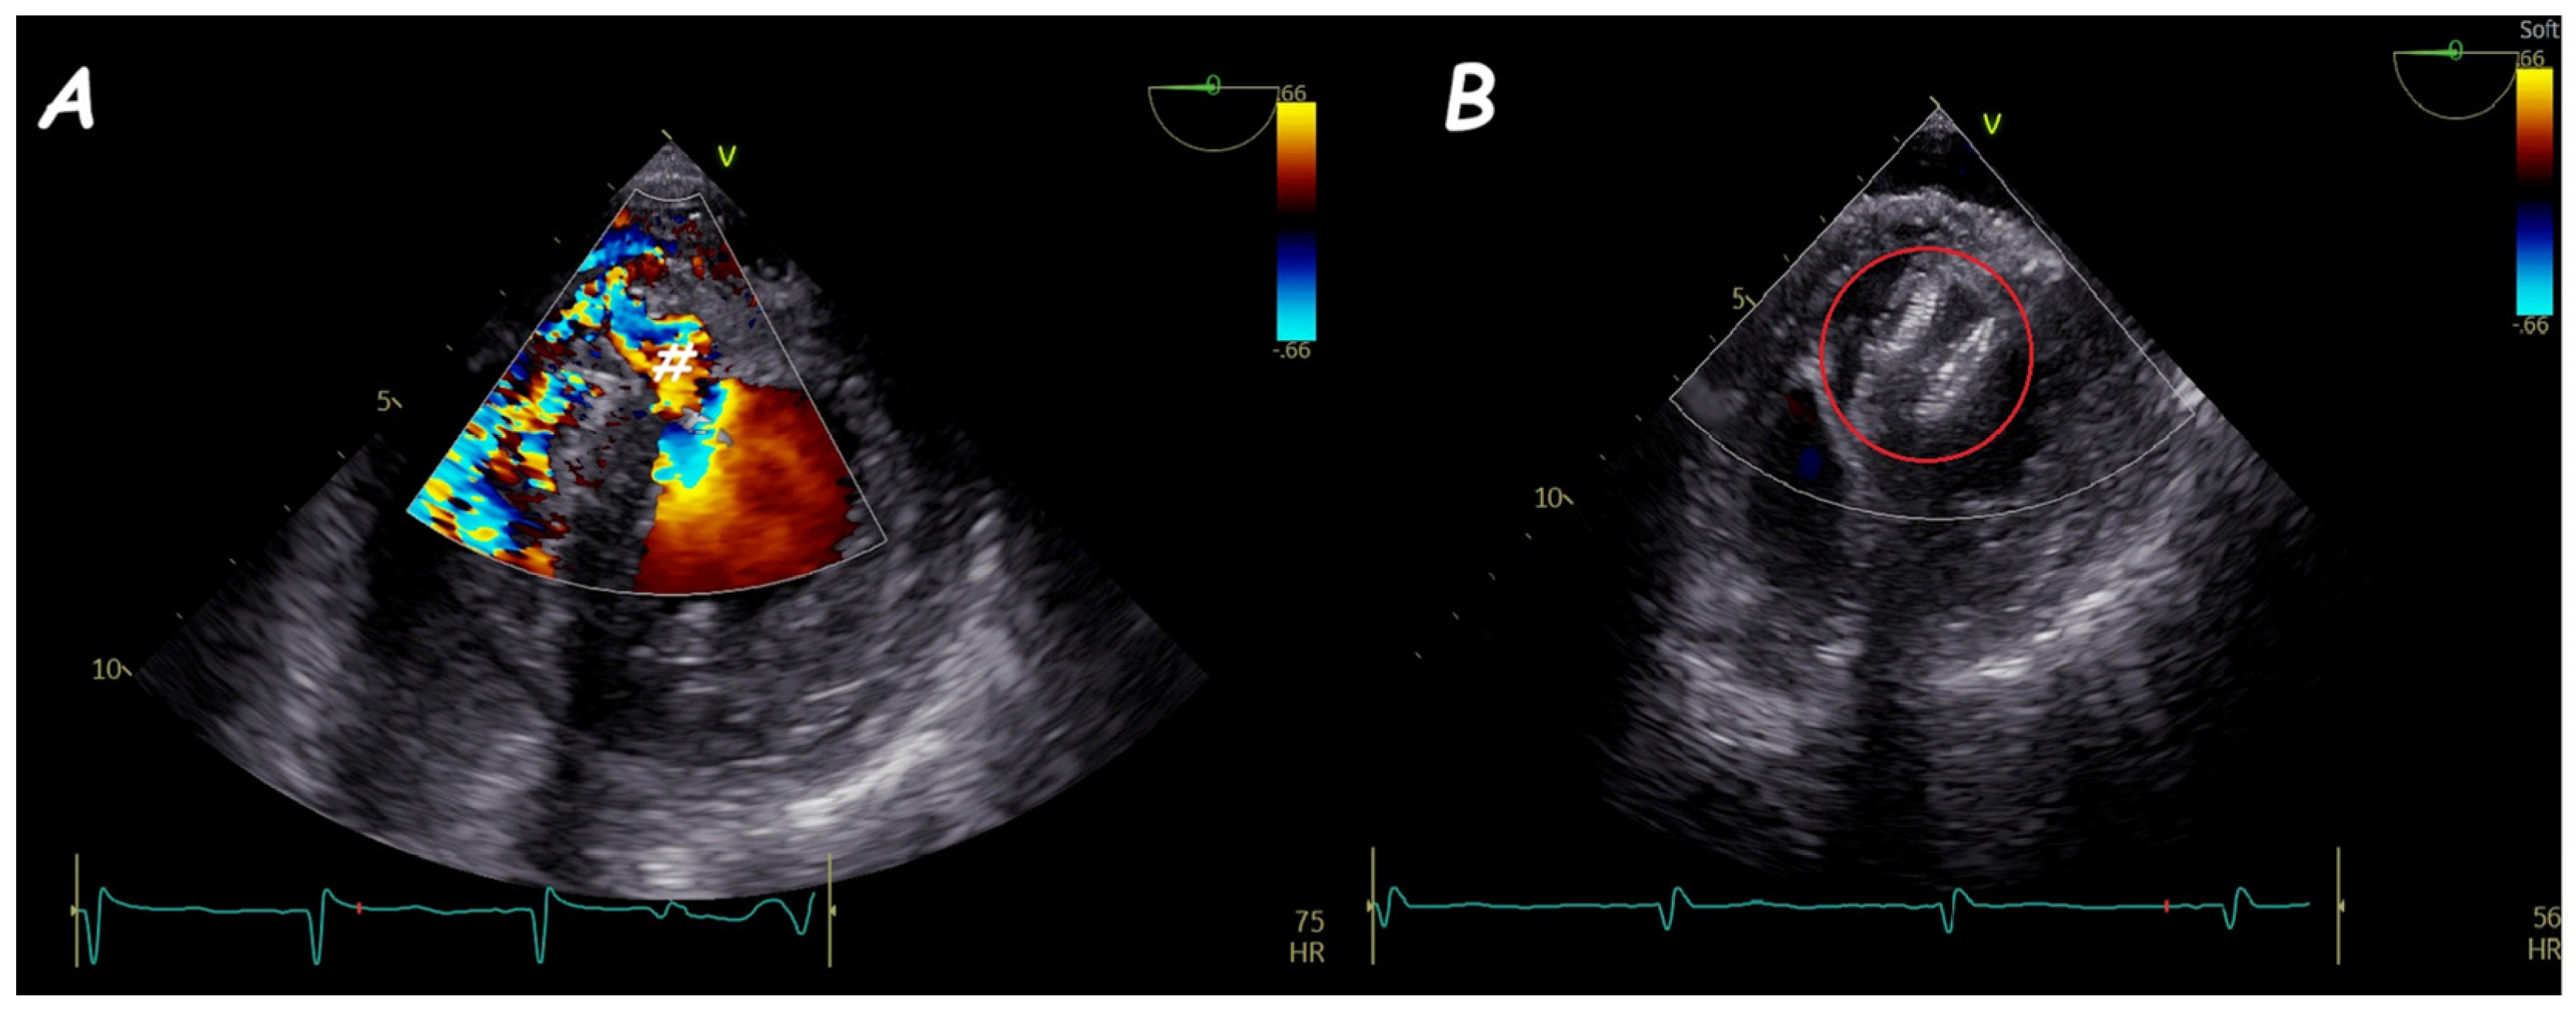

4. Leak Closure of Atrial Switch Operation Baffles

5. Fontan Conduit Fenestration Management